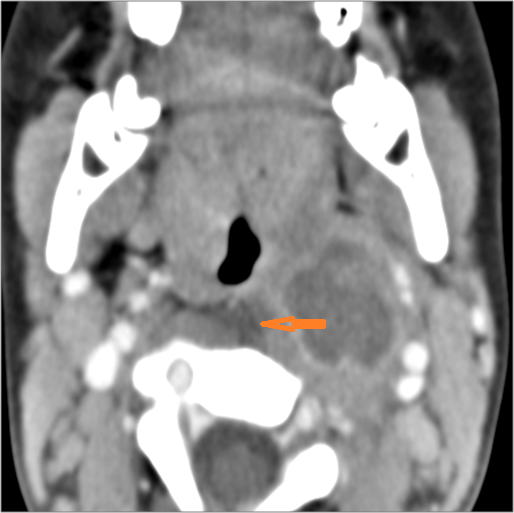

Hypopharynx, Larynx, Deep Neck and Entire Retropharyngeal Space

There is edema within the adjacent deep neck, retropharyngeal and/or prevertebral spaces.

There is abscess within the adjacent deep neck, retropharyngeal and/or prevertebral spaces.